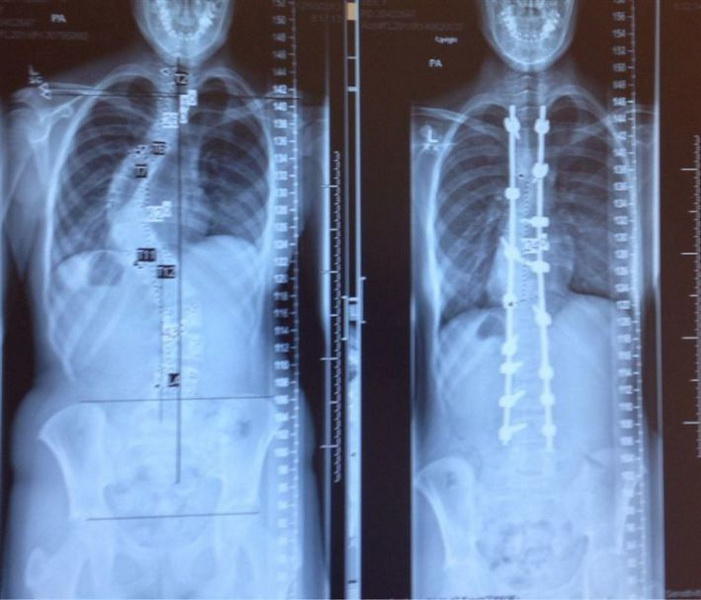

Рентгеновские снимки до и после лечения сколиоза